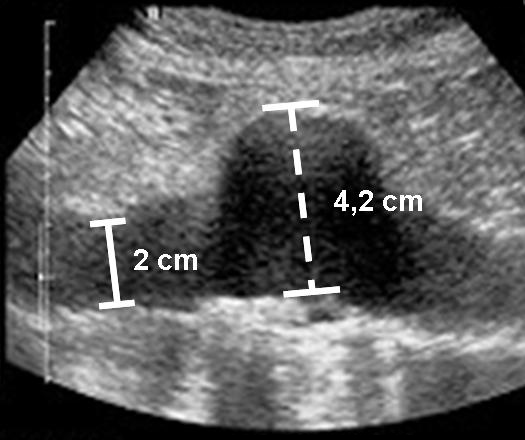

Bei einem Bauchaortenaneurysma erweitert sich die Hauptschlagader im Bauch und entwickelt sich im Lauf der Zeit zu einer immer dünnwandigeren Aussackung. Bleibt die Gefäßerkrankung unerkannt, droht die Schwachstelle zu reißen. „Die Betroffenen laufen dann Gefahr innerhalb kürzester Zeit innerlich zu verbluten“, weiß Prof. Dr. Richard Kellersmann, Leiter der Sektion Gefäßchirurgie an der Klinik und Poliklinik für Allgemein-, Viszeral-, Gefäß- und Kinderchirurgie des Universitätsklinikums Würzburg (UKW). Im Jahr 2011 starben in Deutschland über 3 600 Menschen infolge eines Bauchaortenaneurysmas. „In vielen Fällen hätte durch eine einfache Ultraschalluntersuchung die Gefahr rechtzeitig erkannt und das Leben der Patienten gerettet werden können“, ist sich Prof. Kellersmann sicher.

Zu einer offenen Operation oder der Implantation einer Stentprothese raten die Experten, wenn das Aneurysma einen bestimmten Durchmesser oder ein rasches Wachstum aufweist. Häufig wird dabei ein Stent, eine röhrenförmige Gefäßprothese, über zwei kleine Schnitte in der Leiste implantiert. „Die Medizintechnik hat hier in den letzten Jahren neue, zusätzliche Systeme entwickelt, mit denen auch schwierige ‚Einbausituationen‘ an den Schlagaderabgängen zu Nieren, Darm und Leber gemeistert werden können“, schildert Prof. Kellersmann.